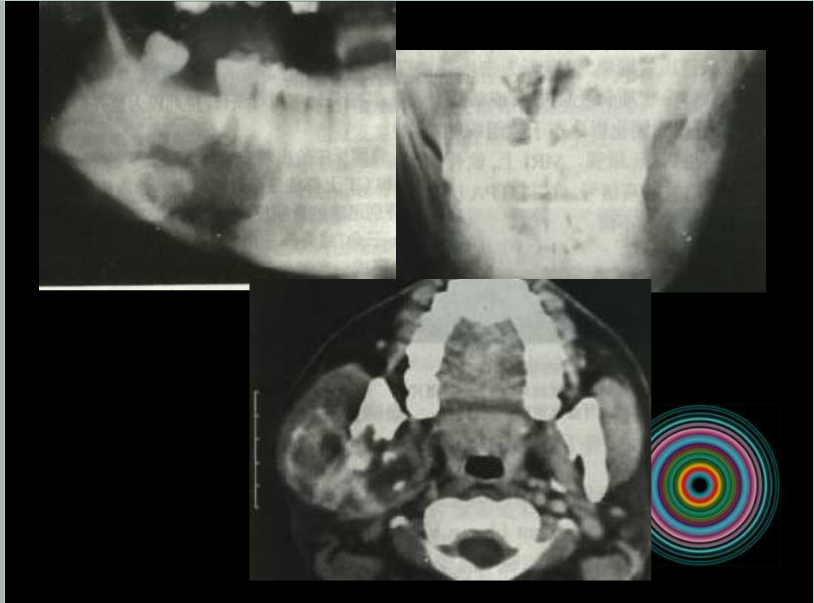

口腔頜面外科 影像技術(shù)